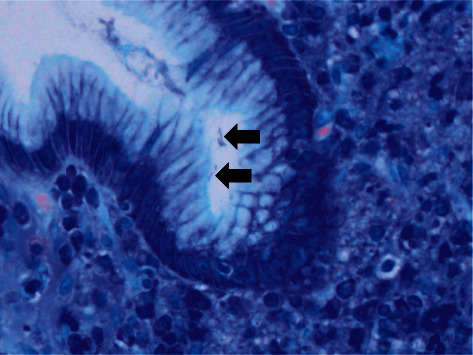

一名45岁的日本男性患者行食管胃十二指肠镜检查,发现胃穹窿斑状发红,粘膜肿胀,胃体弥漫性发红,胃角和胃窦粘膜萎缩。组织学检查显示杆状细菌比幽门螺杆菌大。患者快速脲酶试验阳性,血清抗h抗体阳性。幽门螺杆菌IgG抗体检测结果均为阴性。进一步检测结果显示猪嗜血杆菌抗体检测呈阳性,采用猪嗜血杆菌特异性实时聚合酶链反应证实了猪嗜血杆菌的存在。猪嗜血杆菌经vonoprazan,阿莫西林和克拉霉素三联治疗后被成功根除。这个例子强化了非h。幽门螺杆菌种类,如猪螺杆菌和海氏螺杆菌,可能参与了幽门螺杆菌抗体检测阴性患者活动性胃炎的发病机制。

A 45-year-old Japanese man underwent esophagogastroduodenoscopy, which revealed spotty redness at the gastric fornix, mucosal swelling, diffuse redness in the corpus, and mucosal atrophy in the gastric angle and antrum. Histological examination showed rod-shaped bacteria that appeared larger than Helicobacter pylori. The patient tested positive for rapid urease test, and serum anti-H. pylori IgG antibody test results were negative. Further examination of the bacteria revealed that H. suis antibody test was positive, and the presence of H. suis was confirmed using H. suis-specific real-time PCR. H. suis was successfully eradicated after triple therapy with vonoprazan, amoxicillin, and clarithromycin. This case reinforces the notion that non-H. pylori Helicobacter species such as H. suis and H. heilmannii may be involved in the pathogenesis of active gastritis in patients who test negative for H. pylori antibodies.